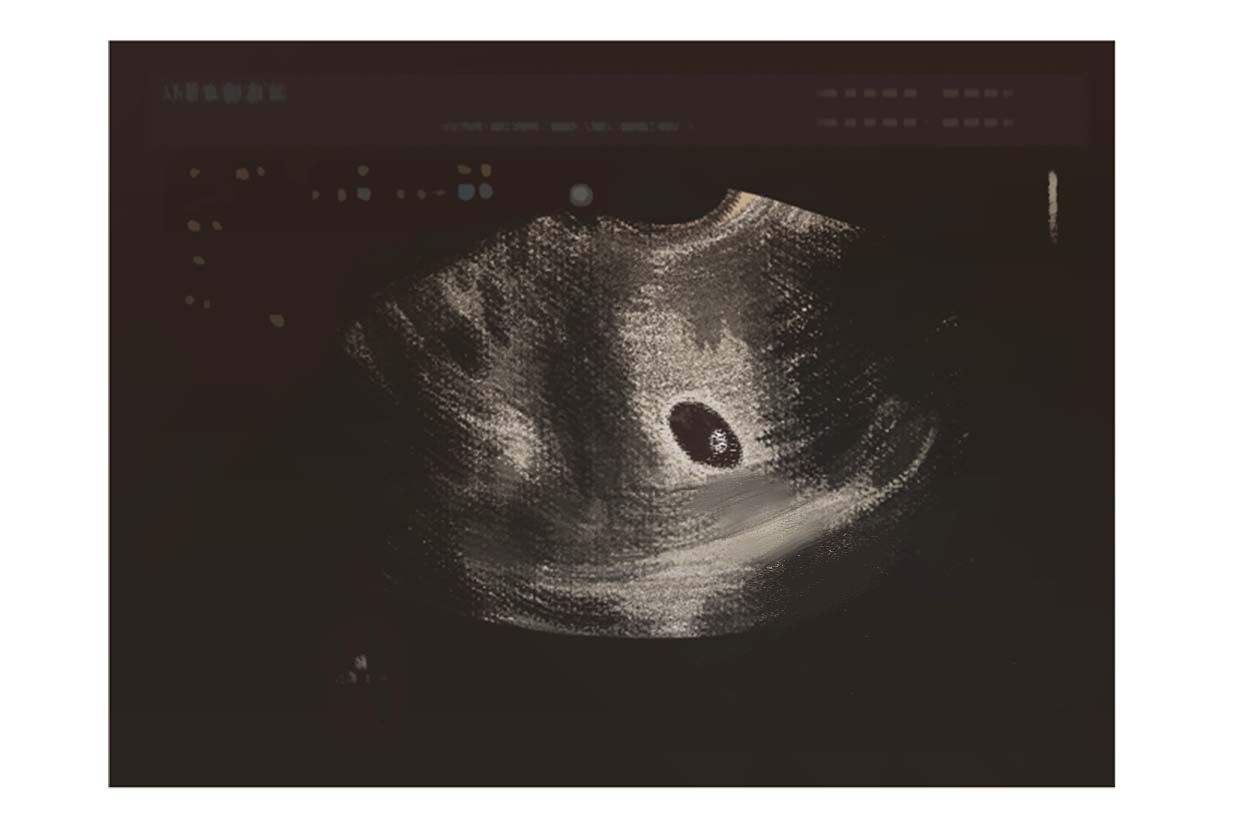

孕囊的形状一般是呈椭圆形或者是月亮型.

女孩; 3,如果胎囊呈椭圆形或茄子形状,多半是男孩;孕囊呈圆形则多半是